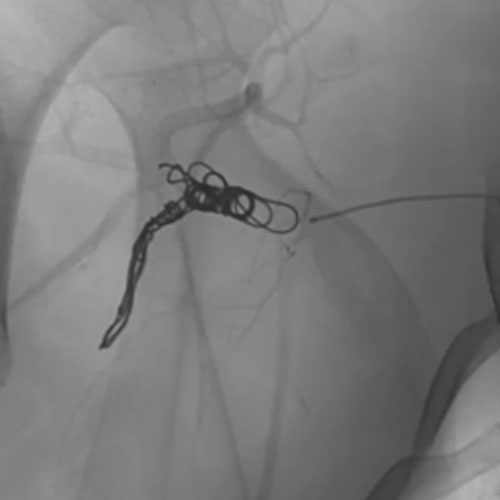

5 vs 3 Coils

Ruby Standard Coil shown in iliac right artery Ruby Standard Coil shown in right internal iliac artery

Right Internal Iliac

Artery

5 Ruby Standard 6x20

Embold Fibered Coil shown in left internal iliac artery Embold Fibered Coil shown in left internal iliac artery

Left Internal Iliac

3 Embold Fibered Coil 6x20